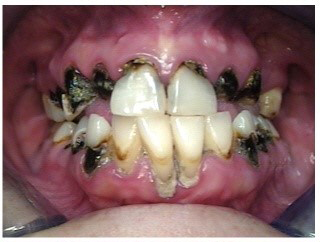

Often, the most visually striking manifestation of long-term meth use—known as “meth mouth”—is caused by the lack of saliva combined with an increase in soda drinking and extremely poor oral hygiene. This typically leads to meth abusers experiencing a large amount of caries. Decay begins with occlusal and facial caries and progresses rapidly, decaying to the bone level and often leaving only roots (Figure 1 through Figure 3).16

Fig 2. Gross oral destruction was the result of more than 20 years of meth use in this 41-year-old woman.

Figure 2